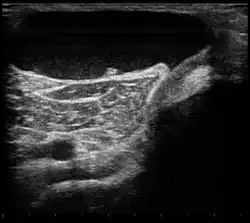

| Ultrasound image of Baker's cyst | |

Diagnosis is by examination. A Baker's cyst is easier to see from behind with the patient standing with knees fully extended. It is most easily palpated (felt) with the knee partially flexed. Diagnosis is confirmed by ultrasonography, although if needed and there is no suspicion of a popliteal artery aneurysm then aspiration of synovial fluid from the cyst may be undertaken with care. An MRI image can reveal presence of a Baker's cyst.